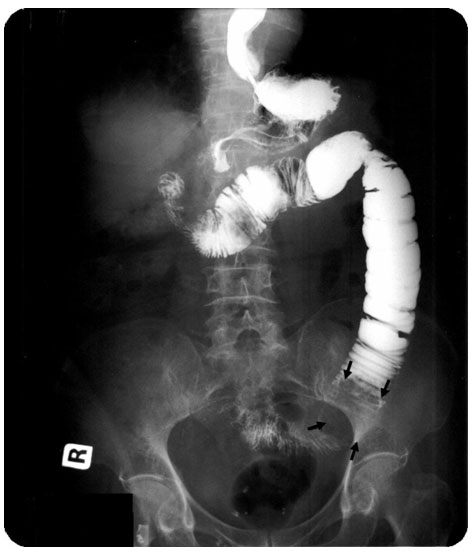

If you eat too little fibre then waste materials do not progress through your gut and get excreted in a timely fashion. If this is the case then you may suffer from constipation. If this is left too long then you may suffer from an impacted bowel. food is going in but no solid matter is being excreted. In extreme cases this can be fatal. The picture below shows an x ray of an impacted bowel.

The white areas are where the x rays are not passing through.